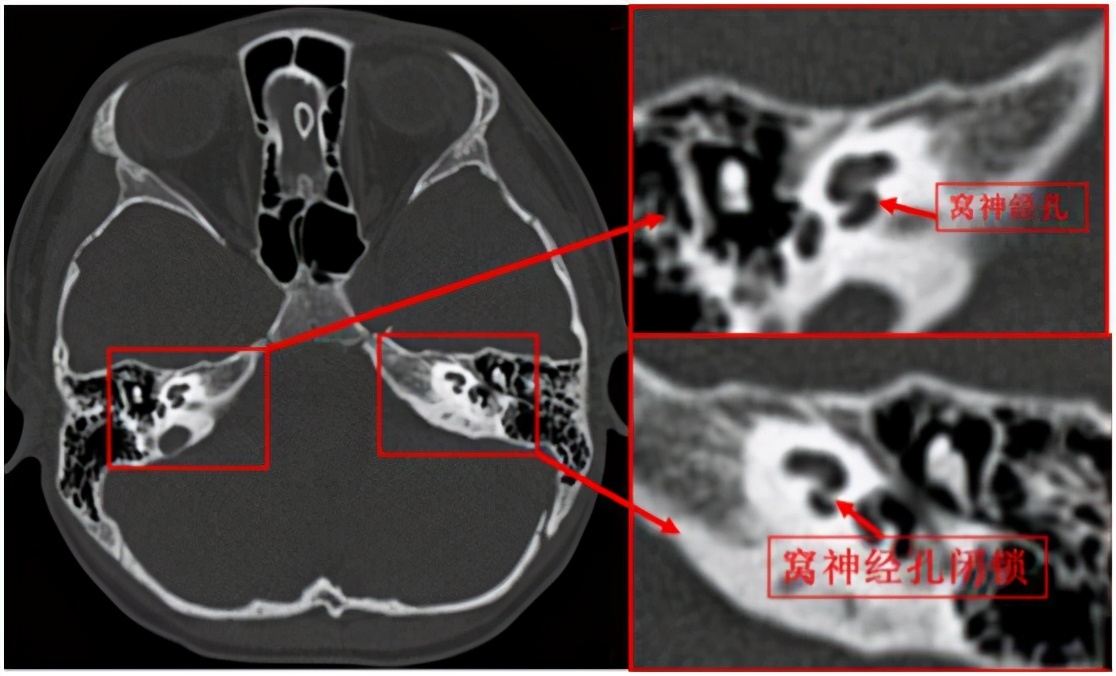

放射科副主任医师李艳梅通过询问患者病史,仔细查看扬扬的磁共振及CT影像,发现左侧蜗神经孔闭锁,蜗神经缺如,结合扬扬的纯音听阈测试结果,放射科主任曾旭文认为,扬扬为左侧耳蜗神经缺如,左侧窝神经孔闭锁。

患者的影像检查 图/医院提供